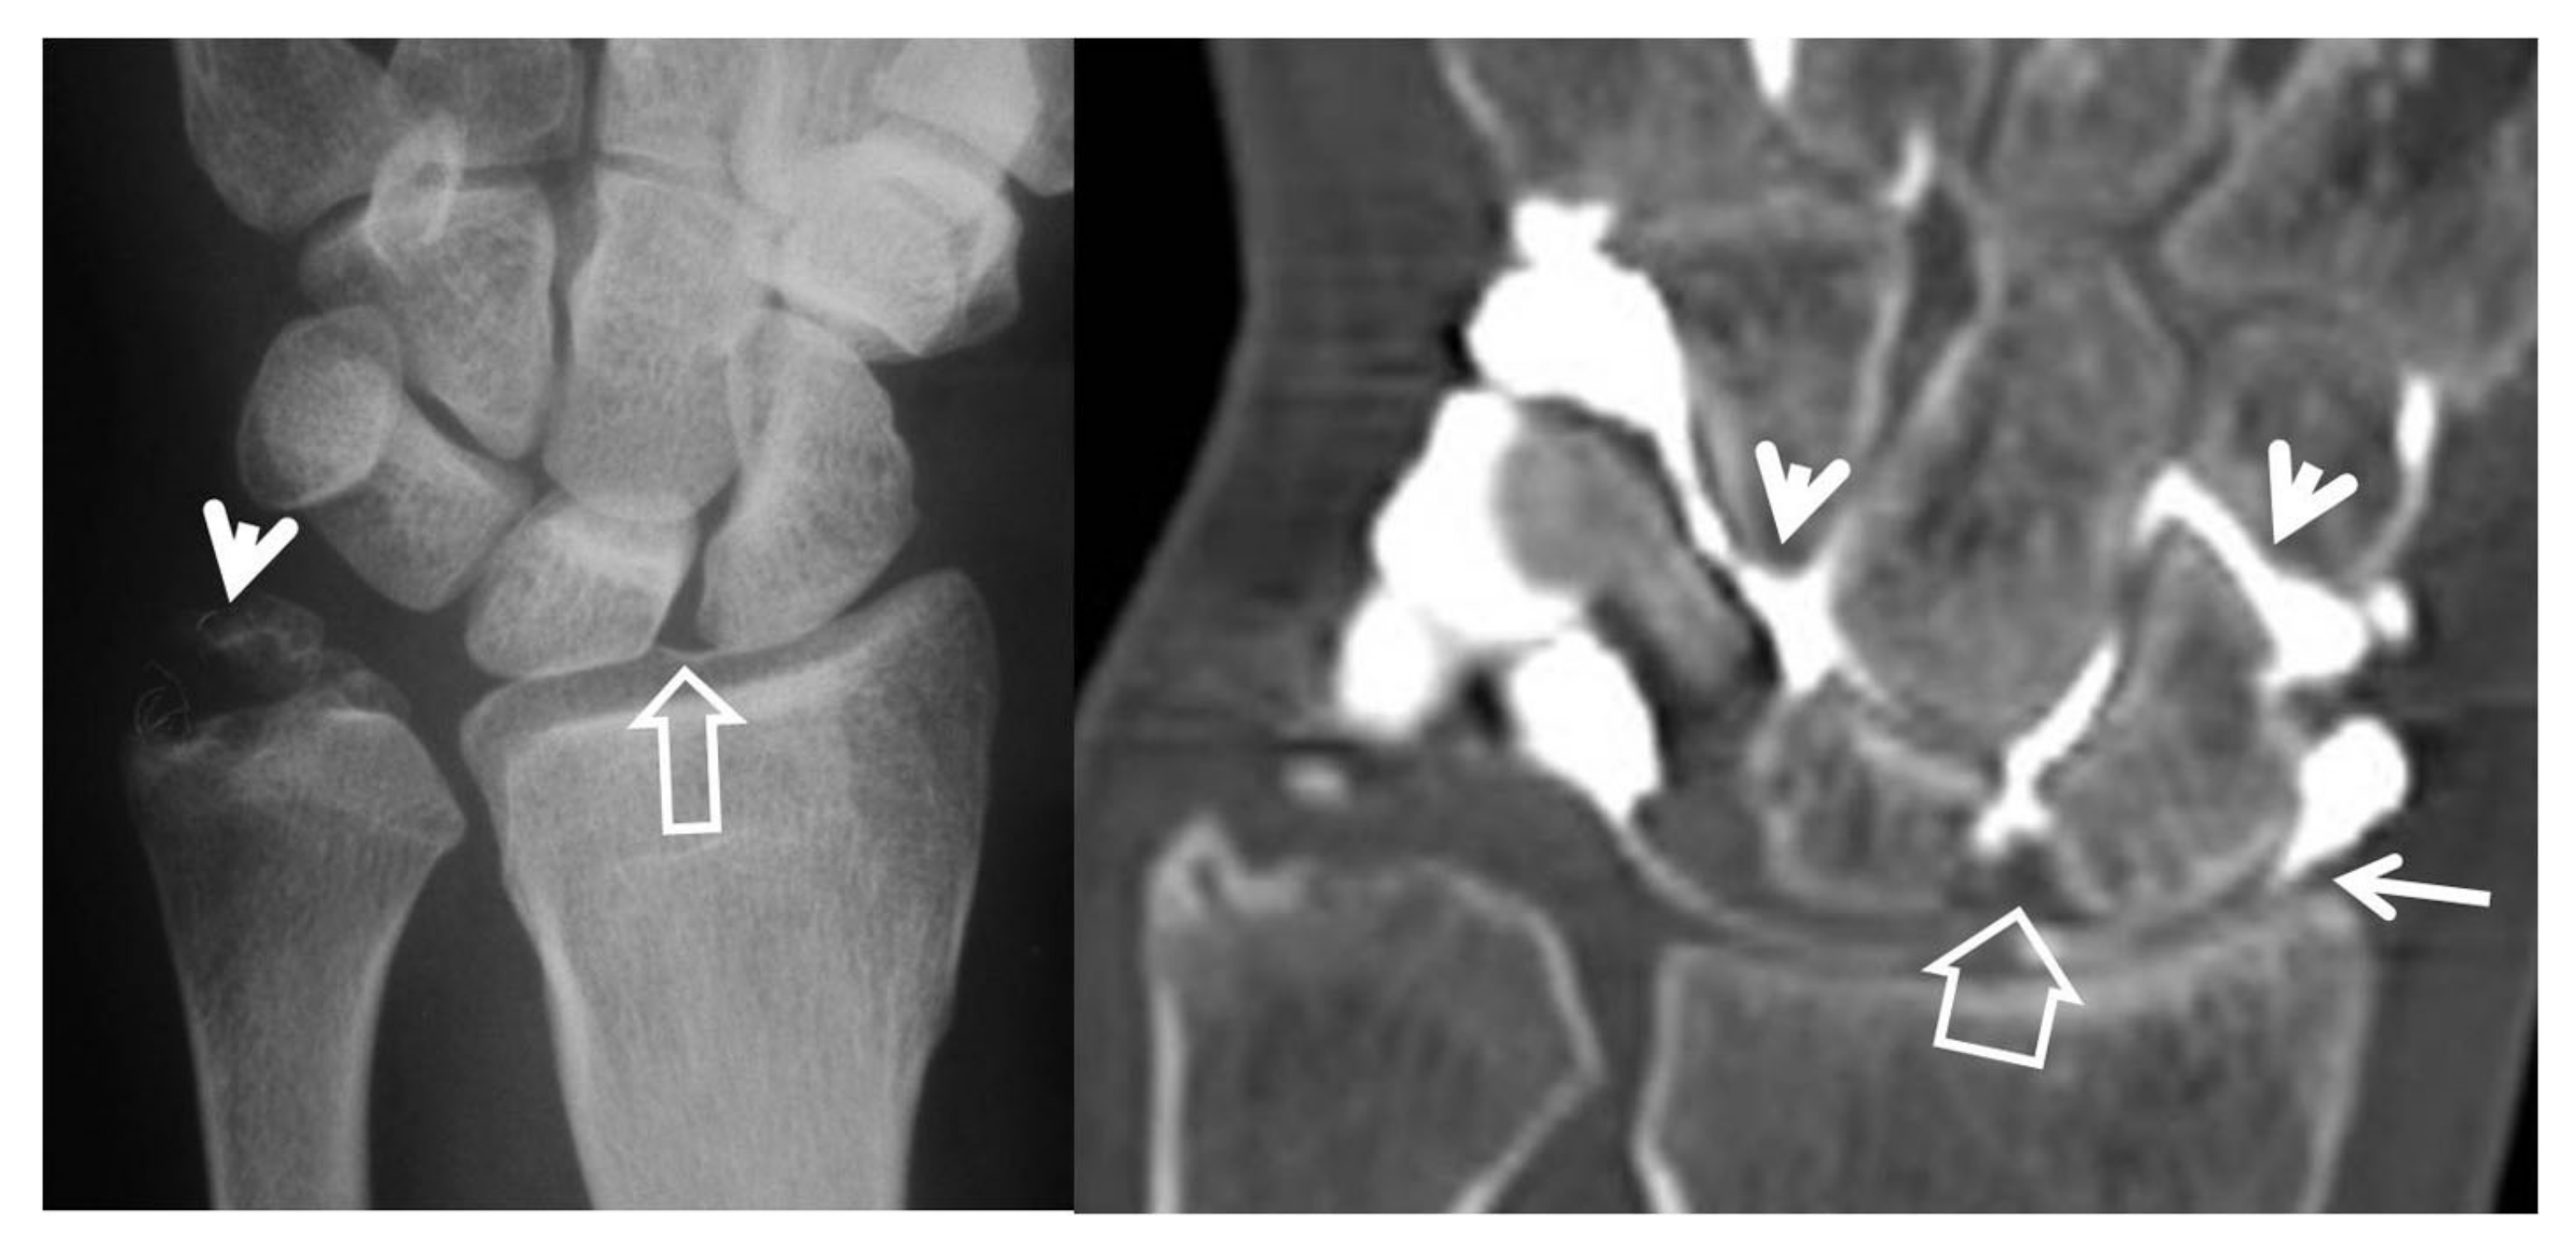

Figure 5.

Scaphoid pseudarthrosis and early SNAC wrist, in this 25-year-old male patient with an injury 4 years prior to current imaging. PA radiograph (A) showing the pseudarthrosis (long arrow), proximal and distal pole osteonecrosis (small arrows) and joint space narrowing at the most radial aspect of the radioscaphoid joint (open arrow). Coronal CT reconstruction (B), showing in addition osteophyte formation of the scaphoid bone (arrow).

Multidetector computed tomography (MDCT) is a valuable tool in evaluating the wrist’s joint spaces, because of its high spatial resolution and the absence of overlapping tissues. Plain MDCT images may show the early degenerative findings, including subchondral bone sclerosis with or without cyst formation (Figure 5, Figure 6 and Figure 7).

Figure 6.

Coronal (A) and sagittal (B) CT reconstructions of a 23-year-old male patient with an injury 7 years prior to current imaging. SNAC wrist is shown with radioscaphoid joint space narrowing with osteophyte formation (large open arrow left, open arrow right), secondary to proximal pole osteonecrosis (small open arrow left) and pseudarthrosis (thin arrow left). Large cyst formation is shown in the distal pole of the scaphoid (arrowheads).